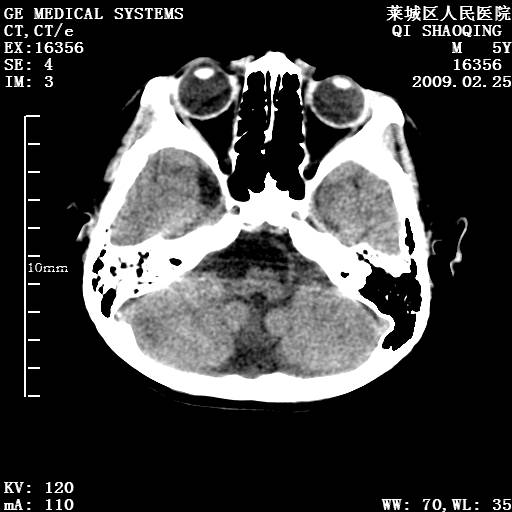

以下是引用wangzhengyuan在2009-2-28 10:22:00的发言:[br]甲状旁腺功能减退引起的脑改变.

以下是引用zsl6918在2009-2-28 10:17:00的发言:[br]首先考虑甲状旁腺功能低下所致,可结合实验室检查明确.另外需除外先天性宫内感染所致.

以下是引用余辉在2009-3-1 9:35:00的发言:[br]患者明显的肢体及智力改变,不支持fahr病,多考虑甲旁低,有可能伴有甲低(呆小症).进一步检查。